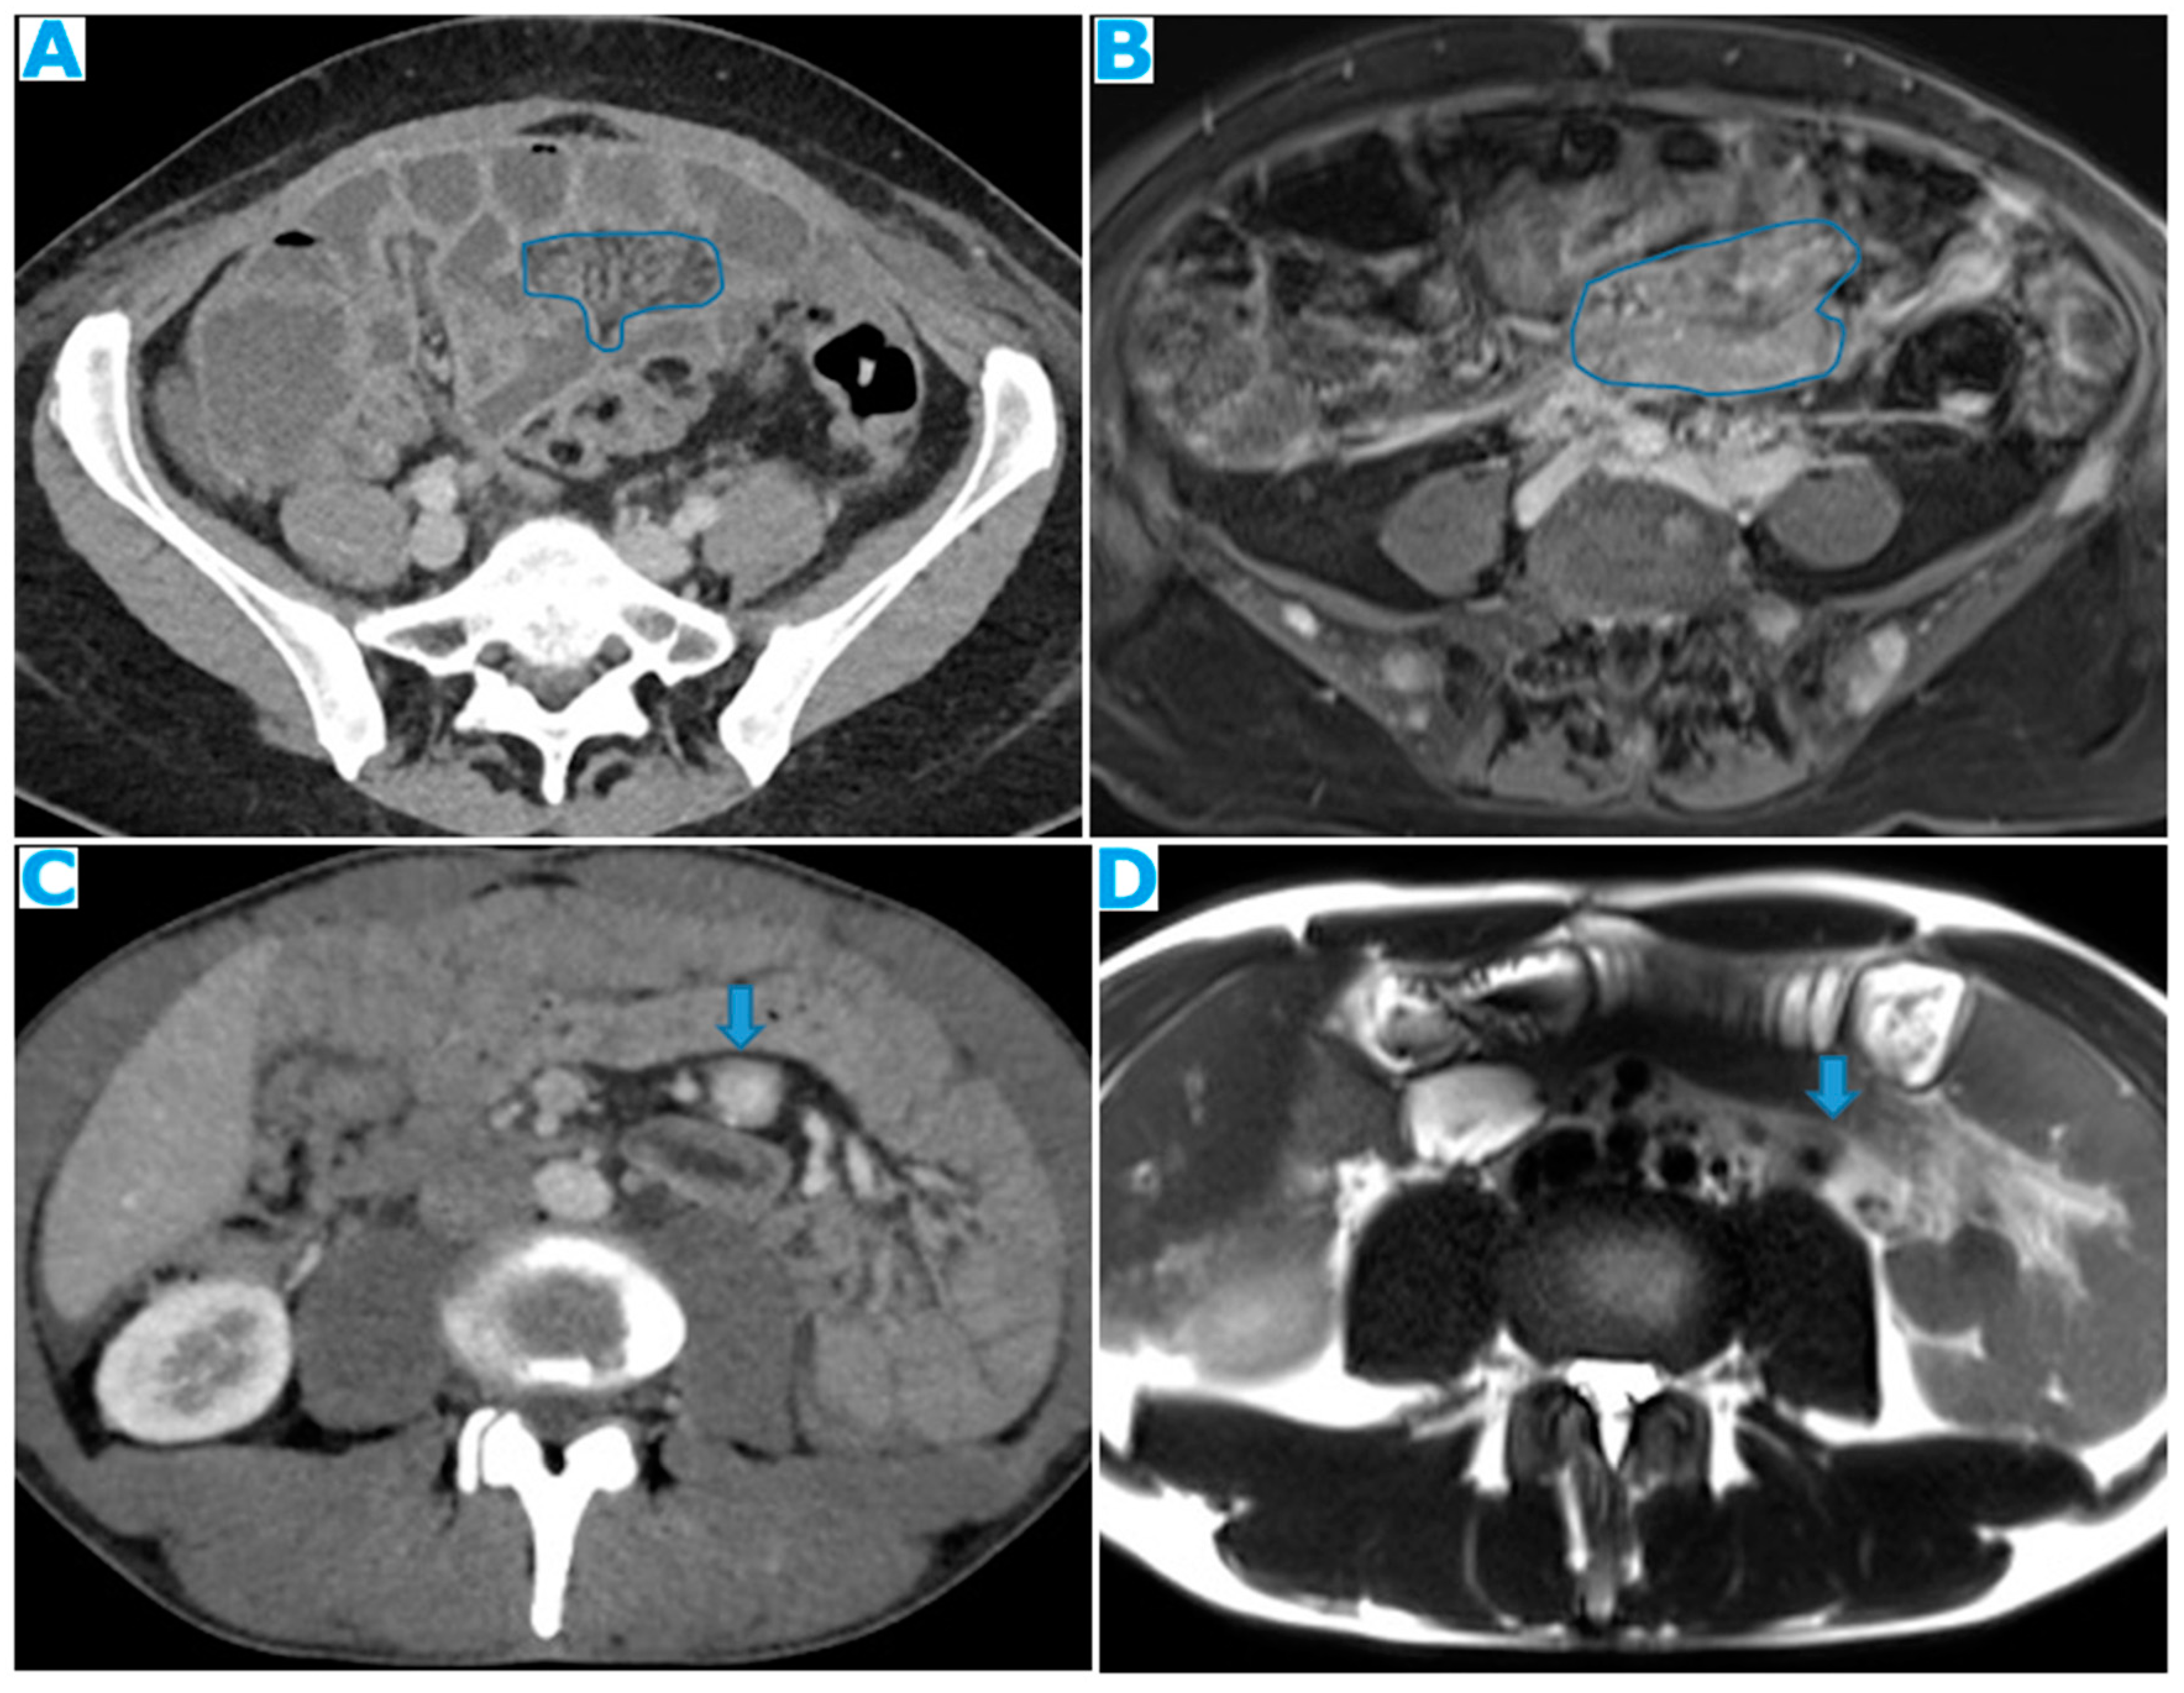

Figure 26.

Axial CE-CT (A). PC from stomach adenocarcinoma: Stellate mesentery. Axial CE portal phase FST1WI (B). PC from lobular breast adenocarcinoma: Stellate mesentery, notice the perivascular distribution. Axial CE-CT (C), axial T2WI (D). PC from stomach adenocarcinoma: Isolated perivascular deposit within the mesentery, as a soft tissue mass surrounding a branch of the SMV.